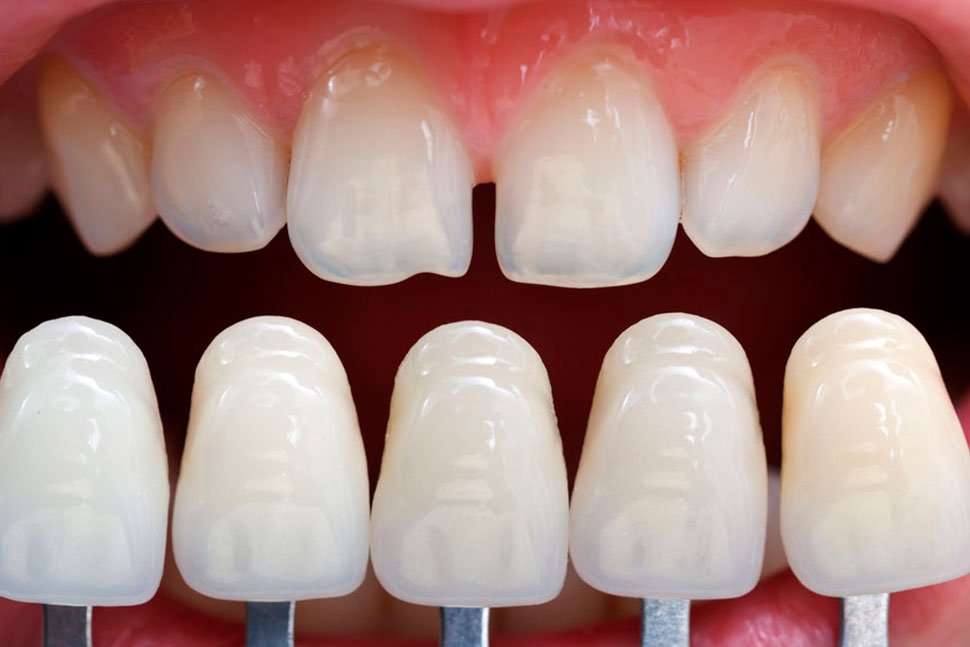

Las carillas E-max son láminas ultradelgadas de cerámica de alta estética que se colocan sobre la superficie frontal de los dientes para mejorar su forma, color, tamaño y proporción. Están fabricadas con disilicato de litio, un material reconocido por su resistencia, translucidez y apariencia natural, muy similar al esmalte dental.

El procedimiento se realiza de manera controlada y cuidadosa. En los casos necesarios, se hace un desgaste mínimo del esmalte para permitir una integración perfecta de las carillas. Posteriormente, las carillas E-max se fabrican a medida y se prueban para verificar ajuste, color y forma. Finalmente, se cementan de forma precisa, asegurando estabilidad, comodidad y una mordida equilibrada. Cada detalle es revisado minuciosamente para lograr una sonrisa natural, estética y funcional, diseñada para durar muchos años.ad.